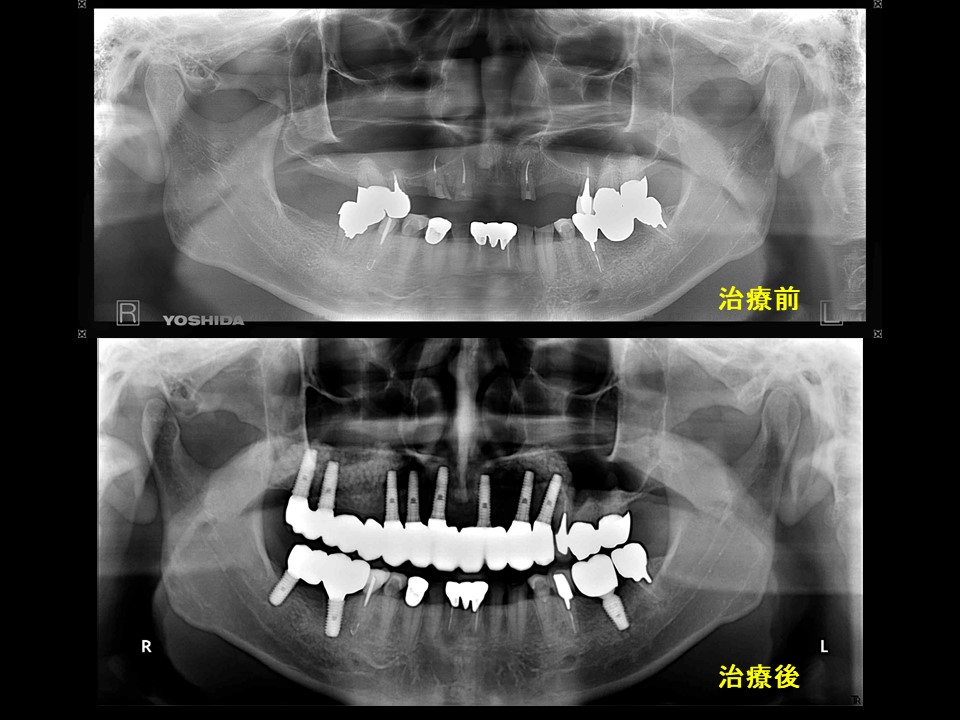

症例28